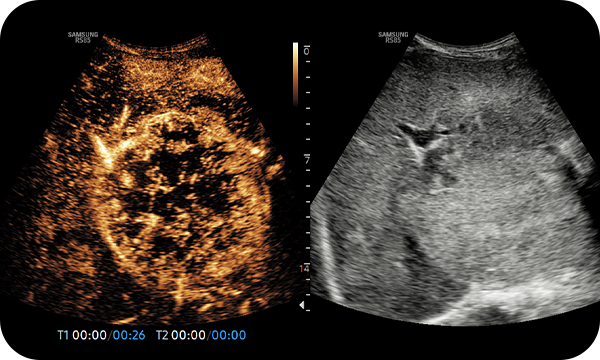

CEUS+ is a contrast enhancement imaging technology that utilizes the characteristics of ultrasound contrast agents. The microbubble contrast agent injected into the body through the vein or alike is subjected to perform nonlinear resonance due to stimulation of ultrasound energy. In addition to the nonlinear signal generated by this method, the ultrasound contrast image is implemented by using the harmonic signal and thus utilized for the diagnosis based on the contrast characteristics over time.